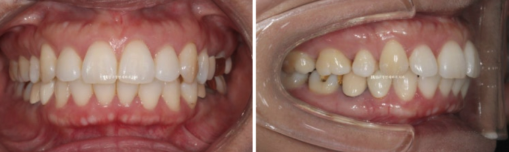

This patient had orthodontic treatment a long time ago.

They are a patient in their 40s who came for orthodontic retreatment in middle age because of protrusion and lip incompetence, where the lips do not close well.

This patient previously had orthodontic treatment, so the alignment and bite are good.

2022.09

After 1 year and 7 months of treatment, here are the before-and-after comparison photos.

Since the original alignment and bite were good, there is not much difference in the intraoral photos other than improvement in the angle of the protruded front teeth.

22.09~24.04